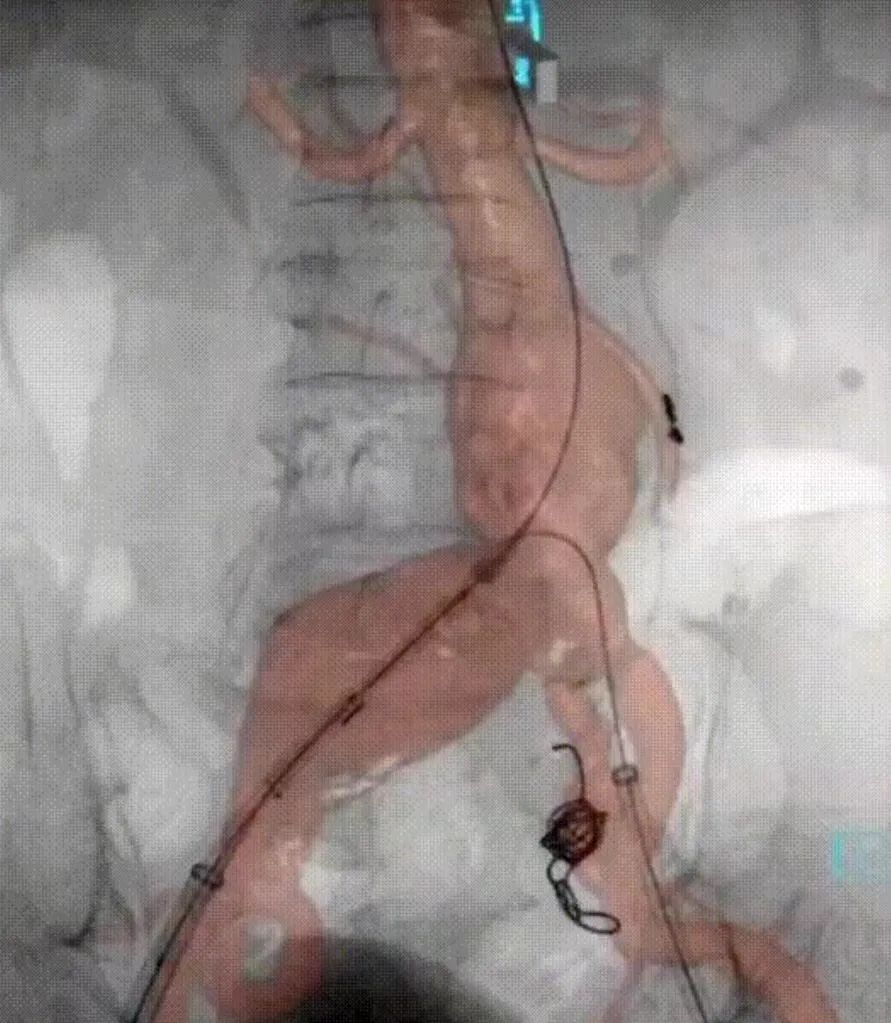

手术中

手术团队为此进行了多次的病例手术方案讨论,从器械的选择、入路的解决到辅助技术的应用,都予以详细的分析并制定相应的预案。最终确定了以IBE+3D影像融合引导下保右侧髂内动脉的EVAR术。基于详尽而充分的术前准备,手术如期而顺利进行,术者通过娴熟的腔内介入技术克服诸多困难,2小时内顺利完成手术,微创的腔内介入使术中出血量不足20ml。患者术后快速恢复,5天后康复出院。

术中3D融合影像引导